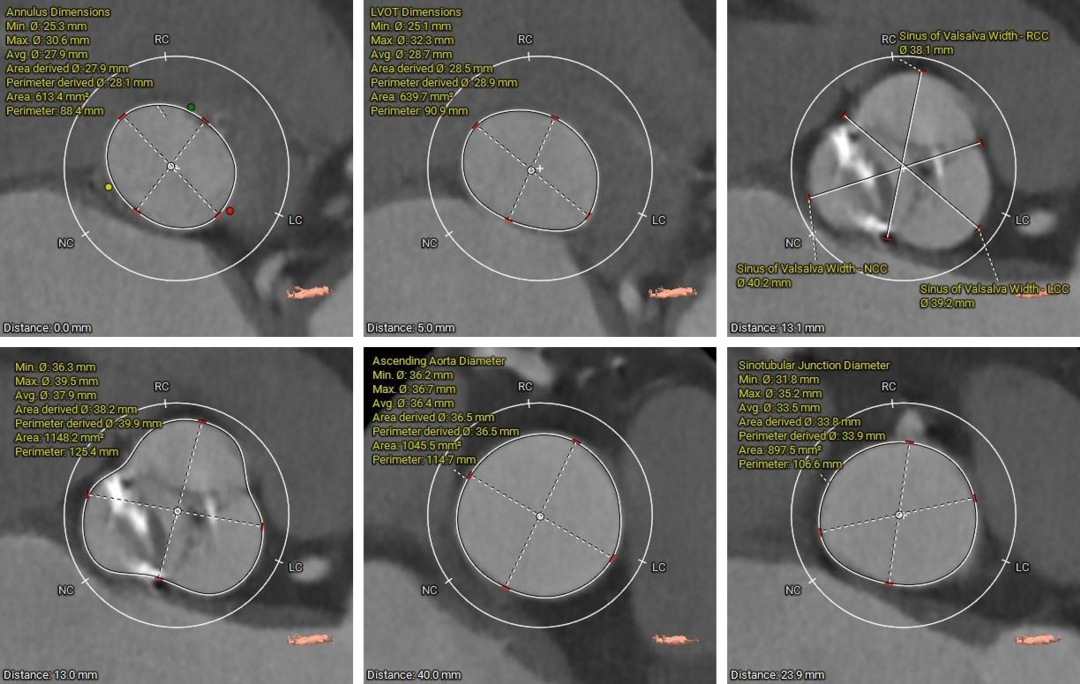

主动脉根部测量

1.Type1型二叶式主动脉瓣,瓣叶增厚伴中度钙化,左右窦间可见钙化融合嵴,钙化主要分布于无冠窦瓣叶边缘以及左右瓣叶交合缘,左室流出道为类直筒型;

3.瓦氏窦、窦管交界、升主动脉内径尚可;

本例患者为主动脉瓣中重度狭窄伴中度反流,患者伴心衰、冠状动脉粥样硬化、扩张性心肌病及脑梗等基础疾病,无法耐受外科开胸手术,术前评估适宜行TAVR手术,有TAVR手术指征。术前CT分析提示患者为Type1型二叶式主动脉瓣,瓣环径较大,达到28.1mm,瓣叶轻度增厚伴重度钙化,瓣上限制较重左右窦瓣叶交合缘可见钙化融合剂,给瓣膜的锚定增加了较大的难度,瓣膜植入后存在形变、移位和瓣周漏的风险。患者为非横位心,升主动脉内径可,输送系统可顺利过弓、跨瓣。此外,该患者全心扩大,EF值为45%,术中循环崩溃风险适中,对术者快速、精准的操作能力及手术团队的密切配合要求较高。